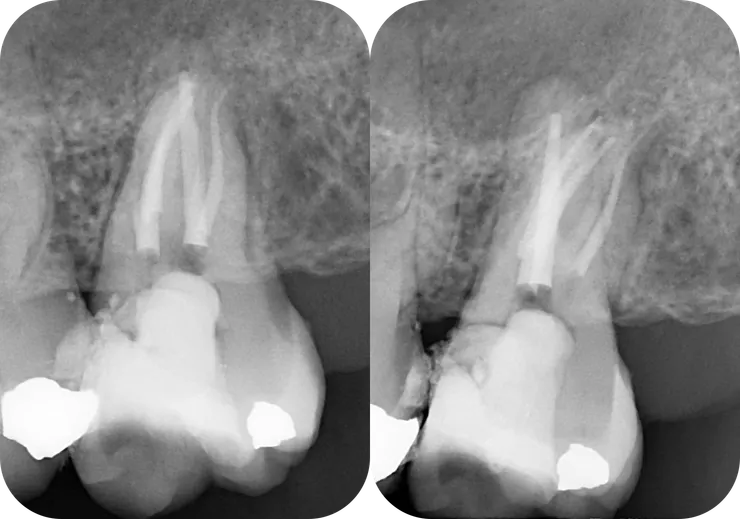

1. 從 initial PA 可以看得出來 36 & 37 的 canal 都細小鈣化到看不到。

2. 第一位 endo 專完成了將近 5 個 canal 後,36 distal apical lesion 有了明顯的癒合。

3. 我接手後完成了 36 的 retreat, mesial apical lesion 也顯著癒合。

而本篇 focus 在 37 的 ML canal.

如同開場白強調的,任何 case 在開始前,務必、千萬、一定要先看清楚 root form (橘色虛線) & canal path (紅線)!

就算 canal 鈣化到看不到,也可以依據 root form 來推測出 canal 可能的走向。

如右圖所示,從依據 root form 推測出的 canal path 看來,原本的路徑似乎偏移不大,是不是繼續往下鑽就可以了呢?